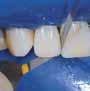

Pre-operative view.First layer placement.Brushing for 20s.

20s polymerization of the first layer.Cavity fill-up.First layer placement of the second restoration.

Table6: Performance criteria according to Ryge. For post-operative sensitivities, mean value and standard deviation is provided (1 = lowest sensitivity, 10 = highest sensitivity) Class I restoration performed with Vertise Flow.

Opti1Step PolisherRestorations after contouring-finishing-polishing.6 months follow

Brushing for 20s.20s final polymerization.Diamond bur 20μ. up.